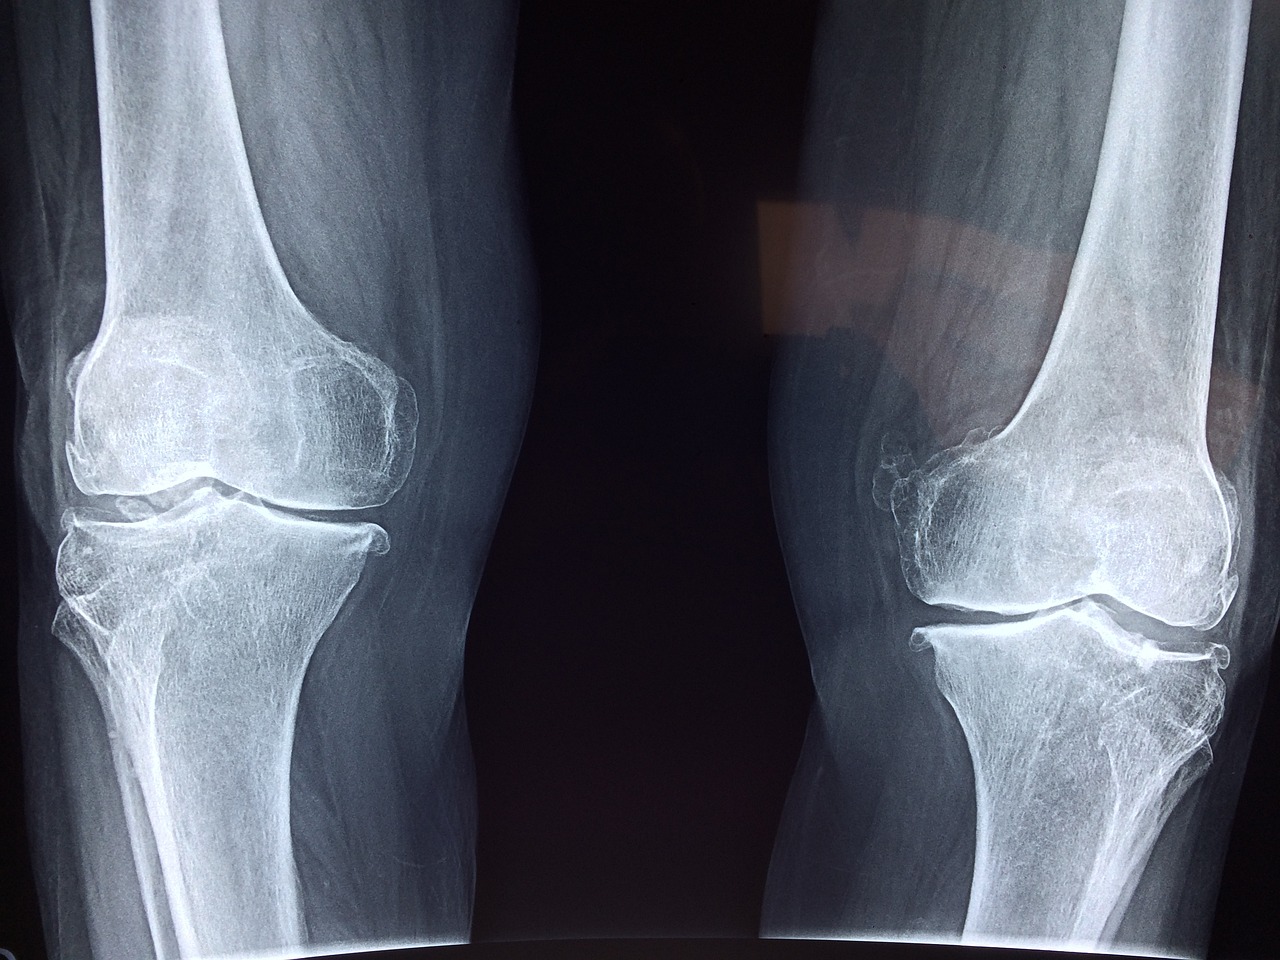

골다공증은 뼈의 양이 줄어들면서 뼈의 강도가 약해지는 현상으로 골절의 위험이 높아지는 질병입니다. 골다공증 환자의 경우 정상인의 뼈 밀도보다 구멍이 크게 뚫려있습니다. 오늘은 골다공증의 원인과 증상 치료방법에 대해 자세히 알아보겠습니다.

2. 골다공증 증상

골다공증 초기에는 크게 인지하지 못합니다. 특별한 증상이 없기 때문입니다. 초기에는 척추뼈가 약해지고 척추변형이나 키가 줄어드는 증상이 발견됩니다. 심해지면 척추가 체중을 이겨내지 못하여 척추가 앞쪽으로 휘어지게 됩니다.

이는 곧 골절로 이러지게 되는 위험을 높이게 됩니다. 심하면 허리를 구부리거나 기침등 간단한 생활에서도 뼈가 쉽게 부러지기도 합니다. 50~70세 여성의 경우 손목골절부터 발생하는 경우가 많습니다. 70세 이후에는 고관절이나 척추골절이 흔하게 발생됩니다.

이렇게 골다공증은 초기에는 증상이 없지만 골절이 생기게되면 통증을 느끼게 되고 골절부위에 다양한 증상이 동반됩니다. 모든 부위에 골절이 일어날 수 있고 손목뼈, 척추, 고관절 골절이 가장 흔하게 나타납니다.